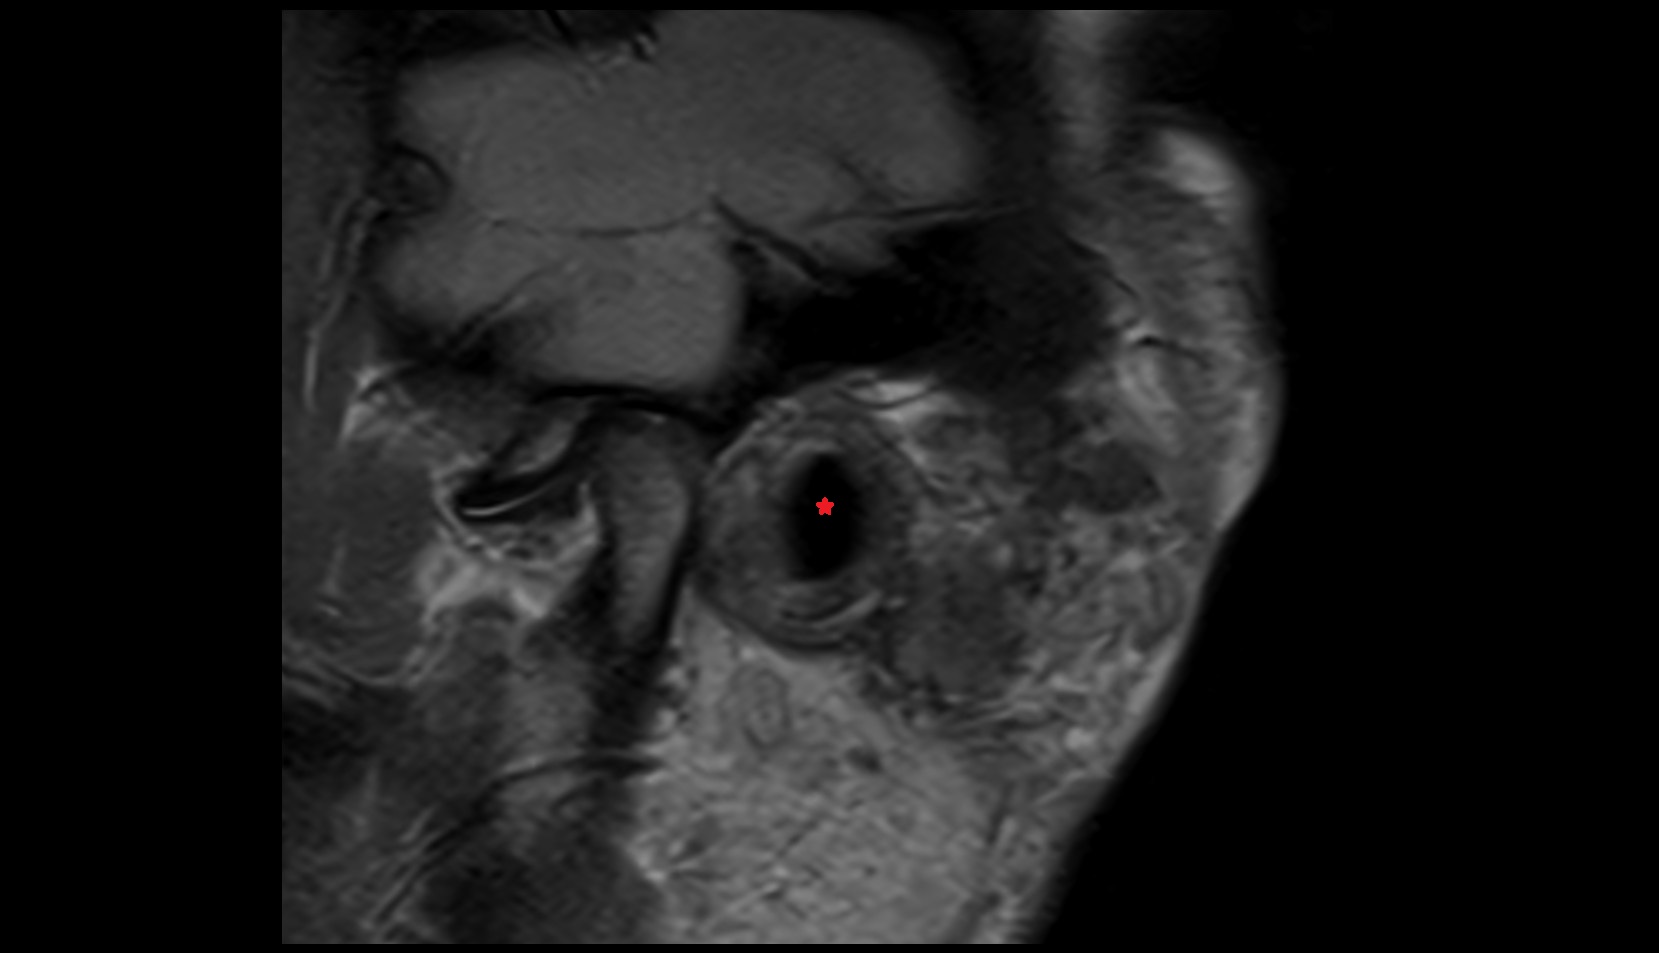

- Mandibular condyle

- Articular disc of temporomandibular joint

- Articular eminence

- Temporomandibular joint